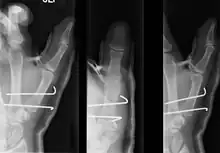

Bennett's fracture

The Bennett fracture is an oblique intraarticular metacarpal fracture dislocation, caused by an axial force directed against the partially flexed metacarpal. This type of compression along the metacarpal bone is often sustained when a person punches a hard object, such as the skull or tibia of an opponent, or a wall. It can also occur as a result of a fall onto the thumb. This is a common injury sustained from bike falls, as the thumb is generally extended while around the handle bars. It is also a common injury in car crashes, especially into fixed objects, from the driver holding the steering wheel during impact. The hand moves forward, while the steering wheel rim hyperextends the thumb. Some authors have recently made an assertion against popular belief that the APL tendon is not a deforming force on the Bennett fracture.[3]

Bennett's fracture repair

Though these fractures commonly appear quite subtle or even inconsequential on radiographs, they can result in severe long-term dysfunction of the hand if left untreated. In his original description of this type of fracture in 1882, Bennett stressed the need for early diagnosis and treatment in order to prevent loss of function of the thumb CMC joint, which is critical to the overall function of the hand.[4]

• In the most minor cases of Bennett fracture, there may be only small avulsion fractures, relatively little joint instability, and minimal subluxation of the CMC joint (less than 1 mm). In such cases, closed reduction followed by immobilization in a thumb spica cast and serial radiography may be all that is required for effective treatment.[5]

• For Bennett fractures where there is between 1 mm and 3 mm of displacement at the trapeziometacarpal joint, closed reduction and percutaneous pin fixation (CRPP) with Kirschner wires is often sufficient to ensure a satisfactory functional outcome. The wires are not employed to connect the two fracture fragments together, but rather to secure the first or second metacarpal to the trapezium.

• For Bennett fractures where there is more than 3 mm of displacement at the trapeziometacarpal joint, open reduction and internal fixation (ORIF) is typically recommended.